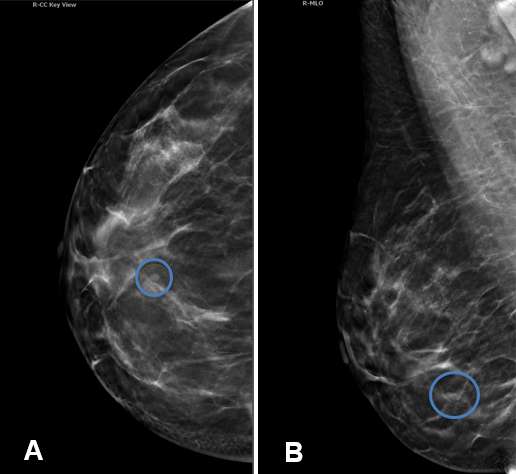

Case: Cysts figure 1

Figure 1A shows a round, well-circumscribed, thin-walled lesion with posterior acoustic enhancement reflect typical imaging features of a simple cyst (red arrow). Figure 1B indicates that the lesion does not exhibit vascularity with color Doppler. Figures 1C and 1D show an additional example of an anechoic lesion with distinct margins, posterior acoustic enhancement and no vascularity, compatible with a simple cyst.